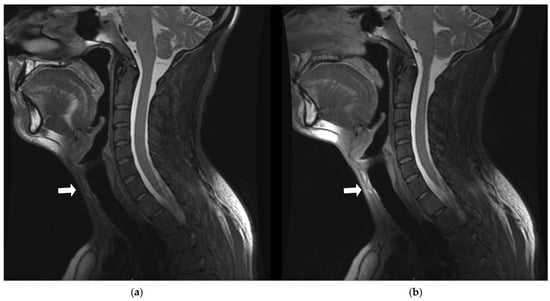

3.3.3. Coil Placement